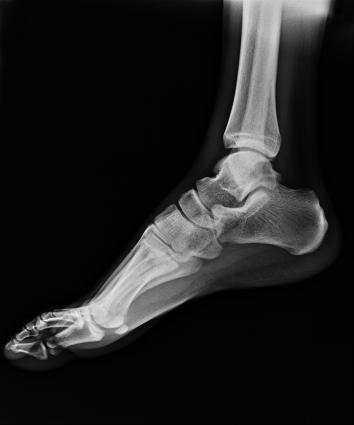

電動旋轉(zhuǎn)內(nèi)平衡結(jié)構(gòu),可實現(xiàn)快捷擺位,滿足特殊體位的靜態(tài)與動態(tài)檢查。